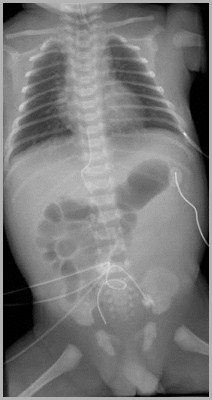

Umbilical venous catheter at junction between IVC and RAUmbilical artery catheter in distal aorta

Auckland